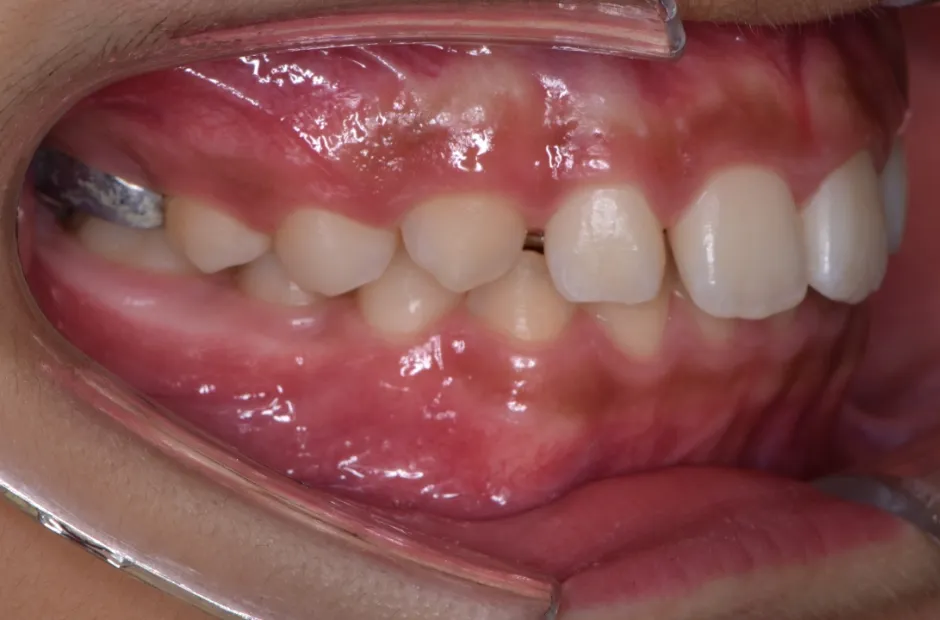

前歯部反対咬合

| 診断名・主訴 | 前歯部反対咬合 |

|---|---|

| 年齢・性別 | 14歳・男性 |

| 治療期間・回数 | 1年2か月 |

| 治療に用いた主な装置 | ブラケット矯正 |

| 抜歯部位 | なし |

| 治療費 | 60万円(税抜) |

| リスク・副作用 | 装置による違和感・疼痛・歯肉退縮・歯根吸収・虫歯のリスクなど |

治療前

治療後